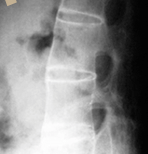

40세 이하 젊은 나이에 아침에 심해지고 활동 후 좋아지는 요통이 3개월 이상 지속되는 환자의 병력, 골반 압박시 통증과 척추 및 흉곽의 운동 범위와 같은 진찰 소견, 그리고 천장 관절의 경화 및 요추가 대나무처럼 굳은 방사선 소견으로 진단을 하게 됩니다. 그래서 어떤 피검사나 방사선촬영만으로 진단을 하는 것은 아닙니다.